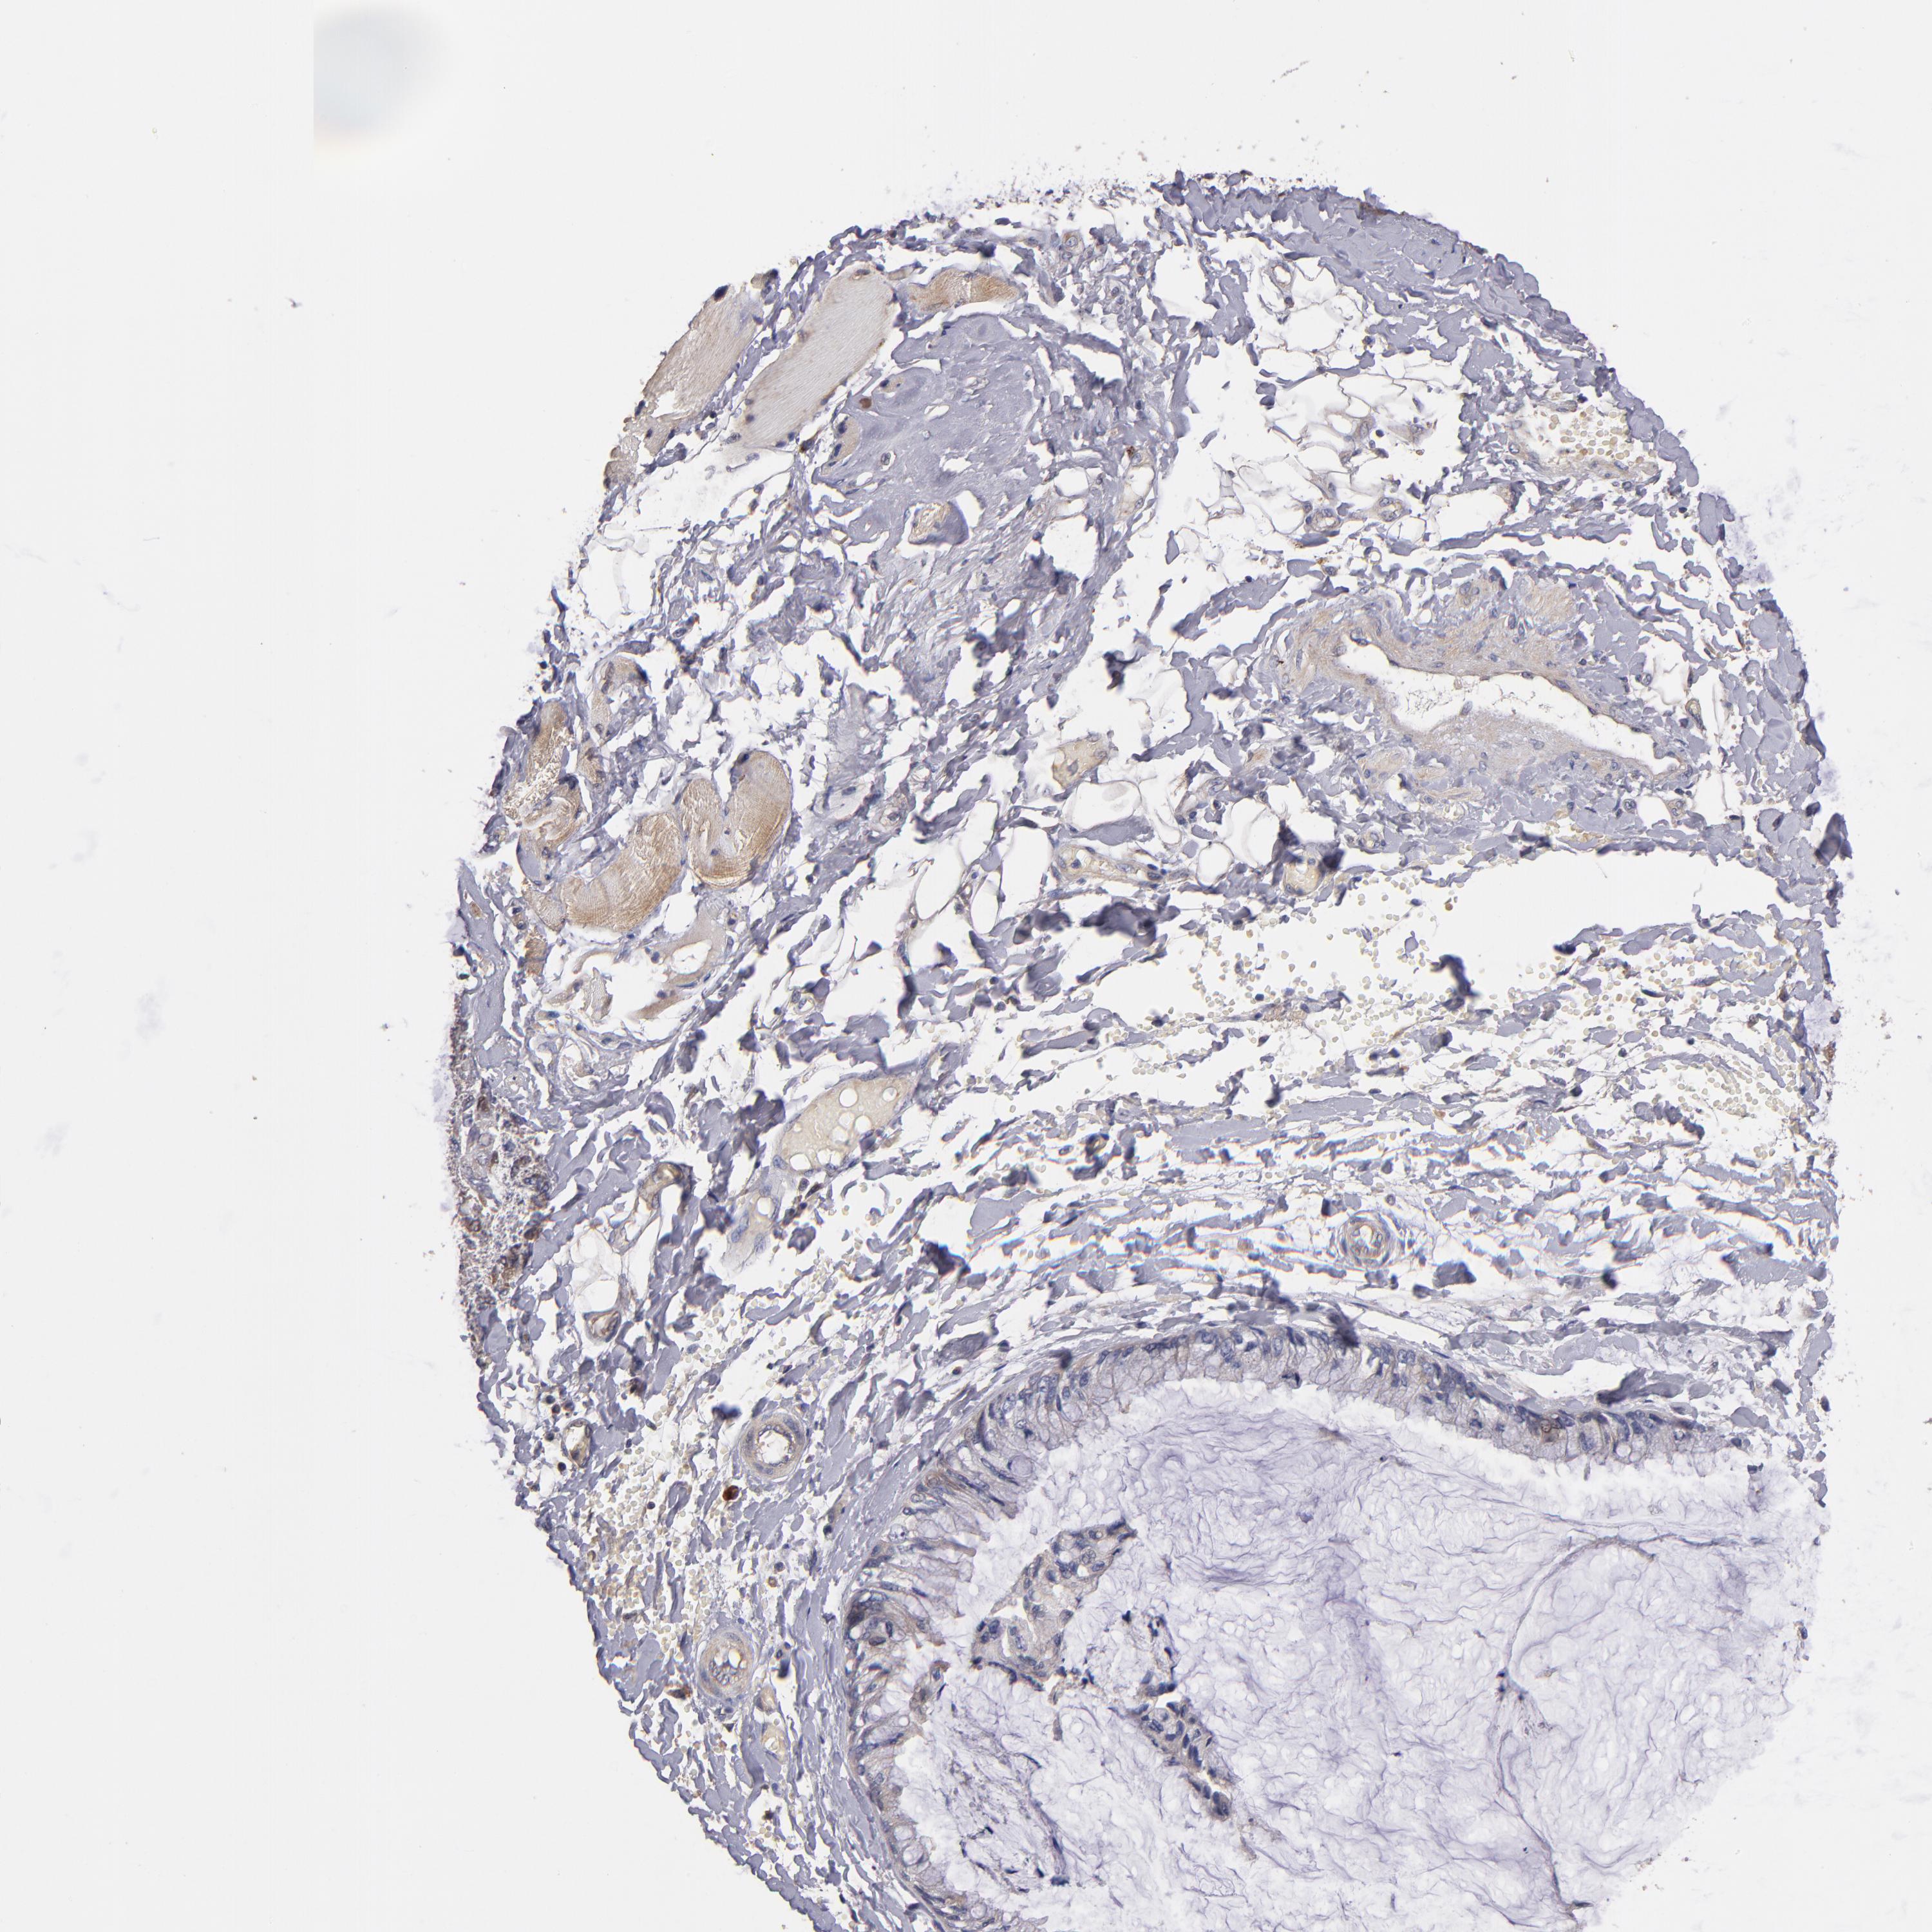

OVARIAN CANCER - Protein expressioni

A mouse-over function shows sample information and annotation data. Click on an image to view it in a full screen mode. Samples can be filtered based on level of antibody staining by selecting one or several of the following categories: high, medium, low and not detected. The assay and annotation is described here.

Note that samples used for immunohistochemistry by the Human Protein Atlas do not correspond to samples in the TCGA dataset.

Antibody stainingi

Antibody staining in the annotated cell types in the current human tissue is reported as not detected, low, medium, or high, based on conventional immunohistochemistry profiling in selected tissues. This score is based on the combination of the staining intensity and fraction of stained cells.

Each image is clickable and will lead to virtual microscopy that enables deeper exploration of all samples and also displays staining intensity scores, fraction scores and subcellular localization as well as patient and tissue information for each sample.

Antibody HPA003047

Staining

High

Medium

Low

Not detected

Intensity

Strong

Moderate

Weak

Negative

Quantity

>75%

75%-25%

<25%

None

Location

Nuclear

Cytoplasmic/membranous

Cytoplasmic/membranous,nuclear

Cystadenocarcinoma, serous, NOS

Cystadenocarcinoma, mucinous, NOS

Carcinoma, endometroid